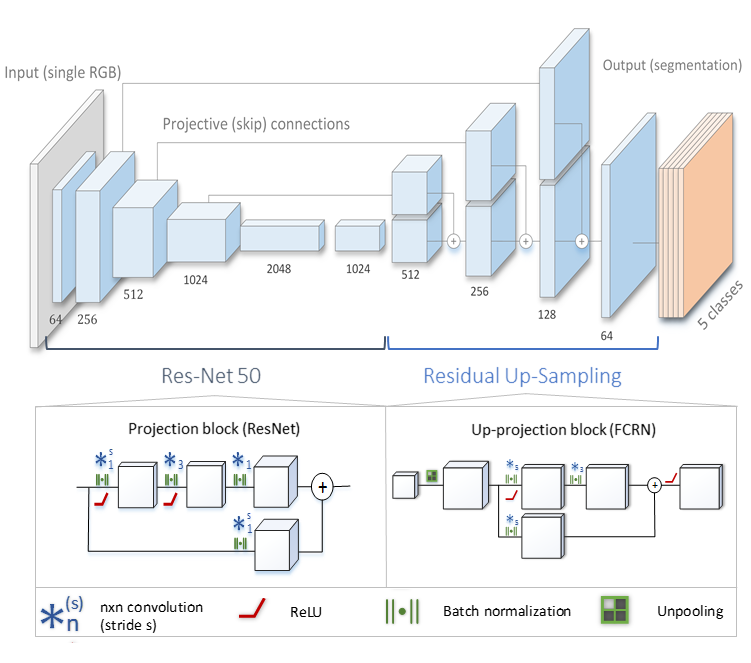

Method 7 was from a team at the Technical University of Munich (TUM) consisting of Nicola Rieke and Iro Laina. The presented method is based on the network for simultaneous segmentation and 2D pose estimation of the instrument that they published with joint first authorship in the main conference [7]. As the challenge data does not provide points of interest to track, the network architecture is reduced to the segmentation-only version of method (see Fig. 8).

The network follows an encoder-decoder structure based on a Fully Convolutional Residual Network (FCRN) [20] with added long-range skip connections. ResNet-50 [21] is used as the encoder, which maps the input frames of resolution to feature maps of lower resolution through a set of residual blocks. The decoder consists of residual up-sampling layers which successively increase the feature map resolution to the output space where they set one output channel per class. To counteract the loss of spatial information due to downsampling, skip connections are added to allow the gradient to bypass part of the network and flow directly from encoding layers to decoding layers. These long-range skip connections reshape the respective encoding layer with a 1x1 convolution and add it to the decoding layer of the same resolution. Separate models are trained for binary segmentation (2 classes) and part segmentation (5 classes).

During training, standard photometric and geometric augmentations are employed to extend the variability of the training dataset. In addition, an application-specific augmentation is introduced to increase the robustness of the proposed model against specular reflections on the instruments which are often the cause of misclassification. Thus, as a form of augmentation, specularities of random strength and size are added along the shaft of the instruments.

In contrast to the original publication, an additional post-processing operation is performed to reduce the noise. Due to the surgical setup, the instruments always enter the recorded scene from one of the image borders. This prior knowledge is included indirectly as a post-processing step by computing the connected components and assigning the background class to spurious instrument predictions that are not connected to the border. Morphological operations are applied to fill holes and make the prediction smoother.

The resulting method runs with near real-time performance on a NVIDIA GeForce GTX TITAN X.